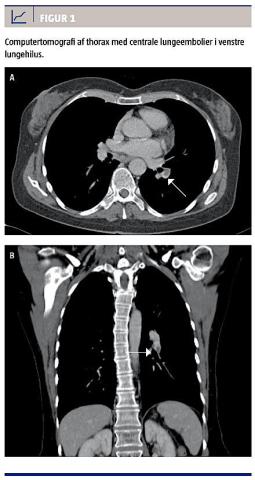

Pga. fortsat manglende diagnostisk afklaring blev der foretaget en computertomografi, som viste centrale LE i venstre lungehilus (Figur 1) og en dyb venøs trombose (DVT) i venstre v. iliaca communis. En ekkokardiografi viste normale forhold. Patienten blev behandlet med dalteparin og warfarin efter vanlige retningslinjer [2], hvorpå man observerede hastigt faldende P-IgE (1.000 k(IE)/l efter fire dages